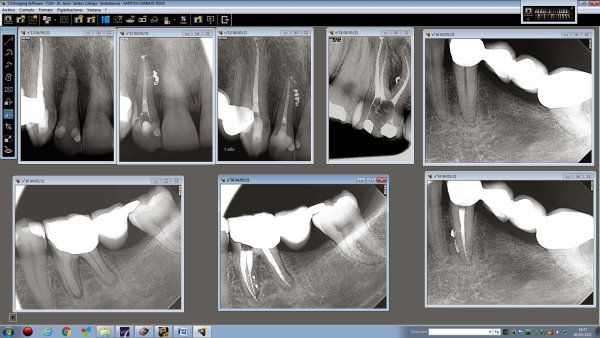

RVG (radiovisiografía)

RVG( radiovisiografia), o también denominada radiología digital, ofrece como ventajas fundamentales con respecto a la radiología convencional un menor tiempo de exposición y una menor dosis de radiación que puede llegar a ser en hasta un 80% menor que la radiología convencional.

Todo ello sin disminuir la resolución y por tanto la calidad de la imagen, para poder completar un correcto diagnóstico.